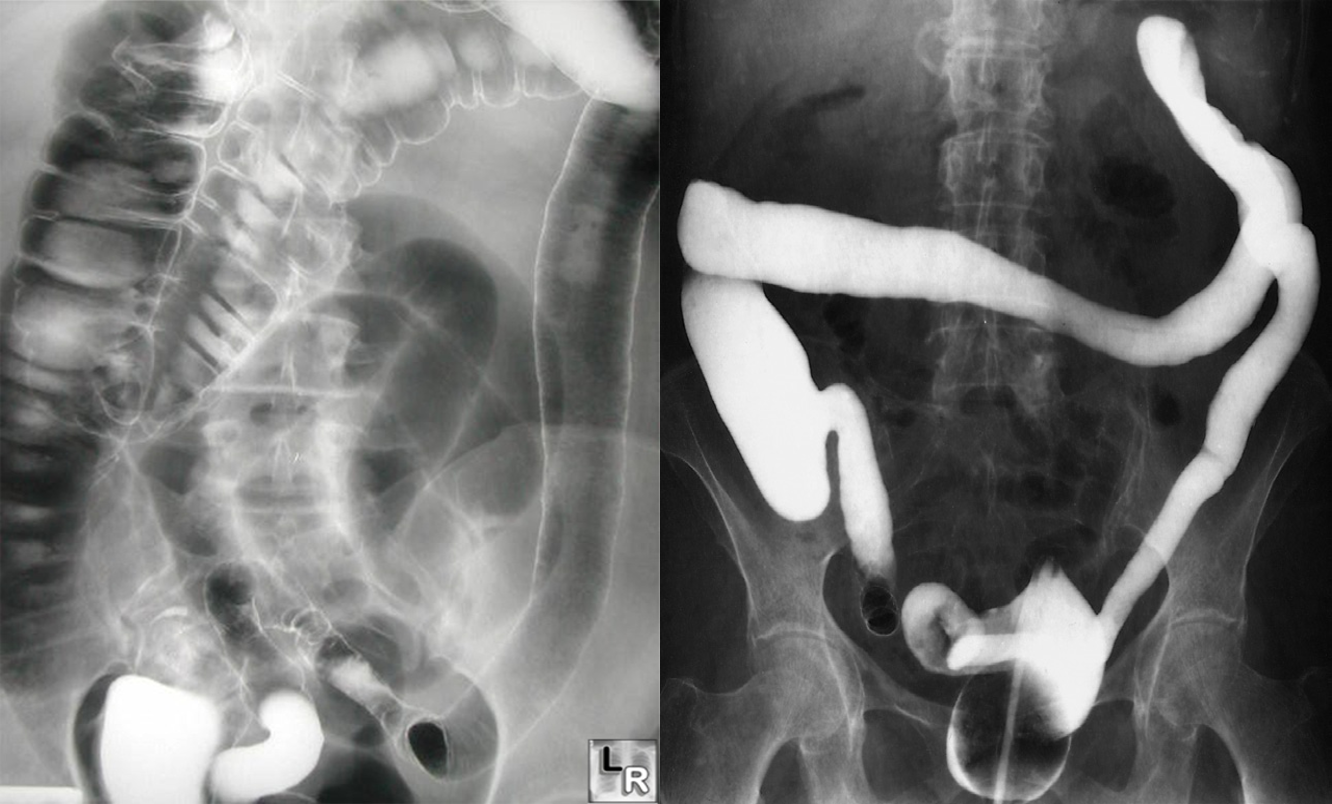

PAIN ABDOMEN AND BLOODY DIARRHEA - ULCERATIVE COLITIS

- Formation of mucosal ulcers (The cardinal radiological sign is widespread ulceration)

- Featureless colon give lead pipe appearances

Ulcerative colitis. With longstanding disease, the haustra are lost and the colon becomes narrowed and shortened, coming to resemble a rigid tube. Reflux into the ileum through an incompetent ileocaecal valve has occurred.

Ulceration. (a) Single contrast. (b) Double contrast.

In this case of ulcerative colitis, the ulceration causes the normally smooth outline of the colon to be irregular